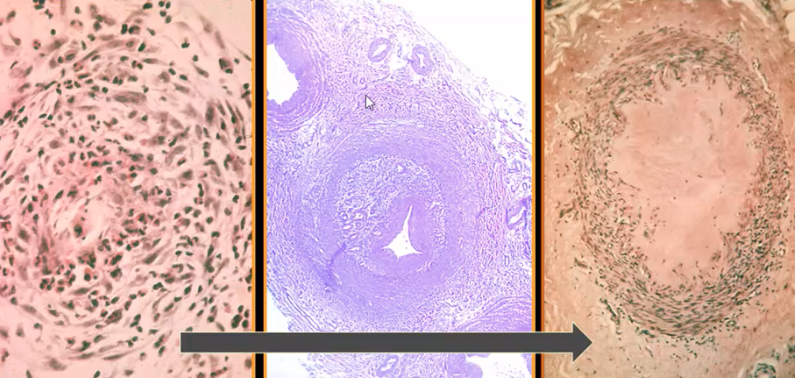

Intima is markedly markedly thick, this is Takayasu arteritis

What are these pictures showing

Tunica media is completely normal whereas the intima is markedly thick, this is takayasu arteritis

Granulomatous inflammation seen in the aorta as part of the Takayasu arteritis